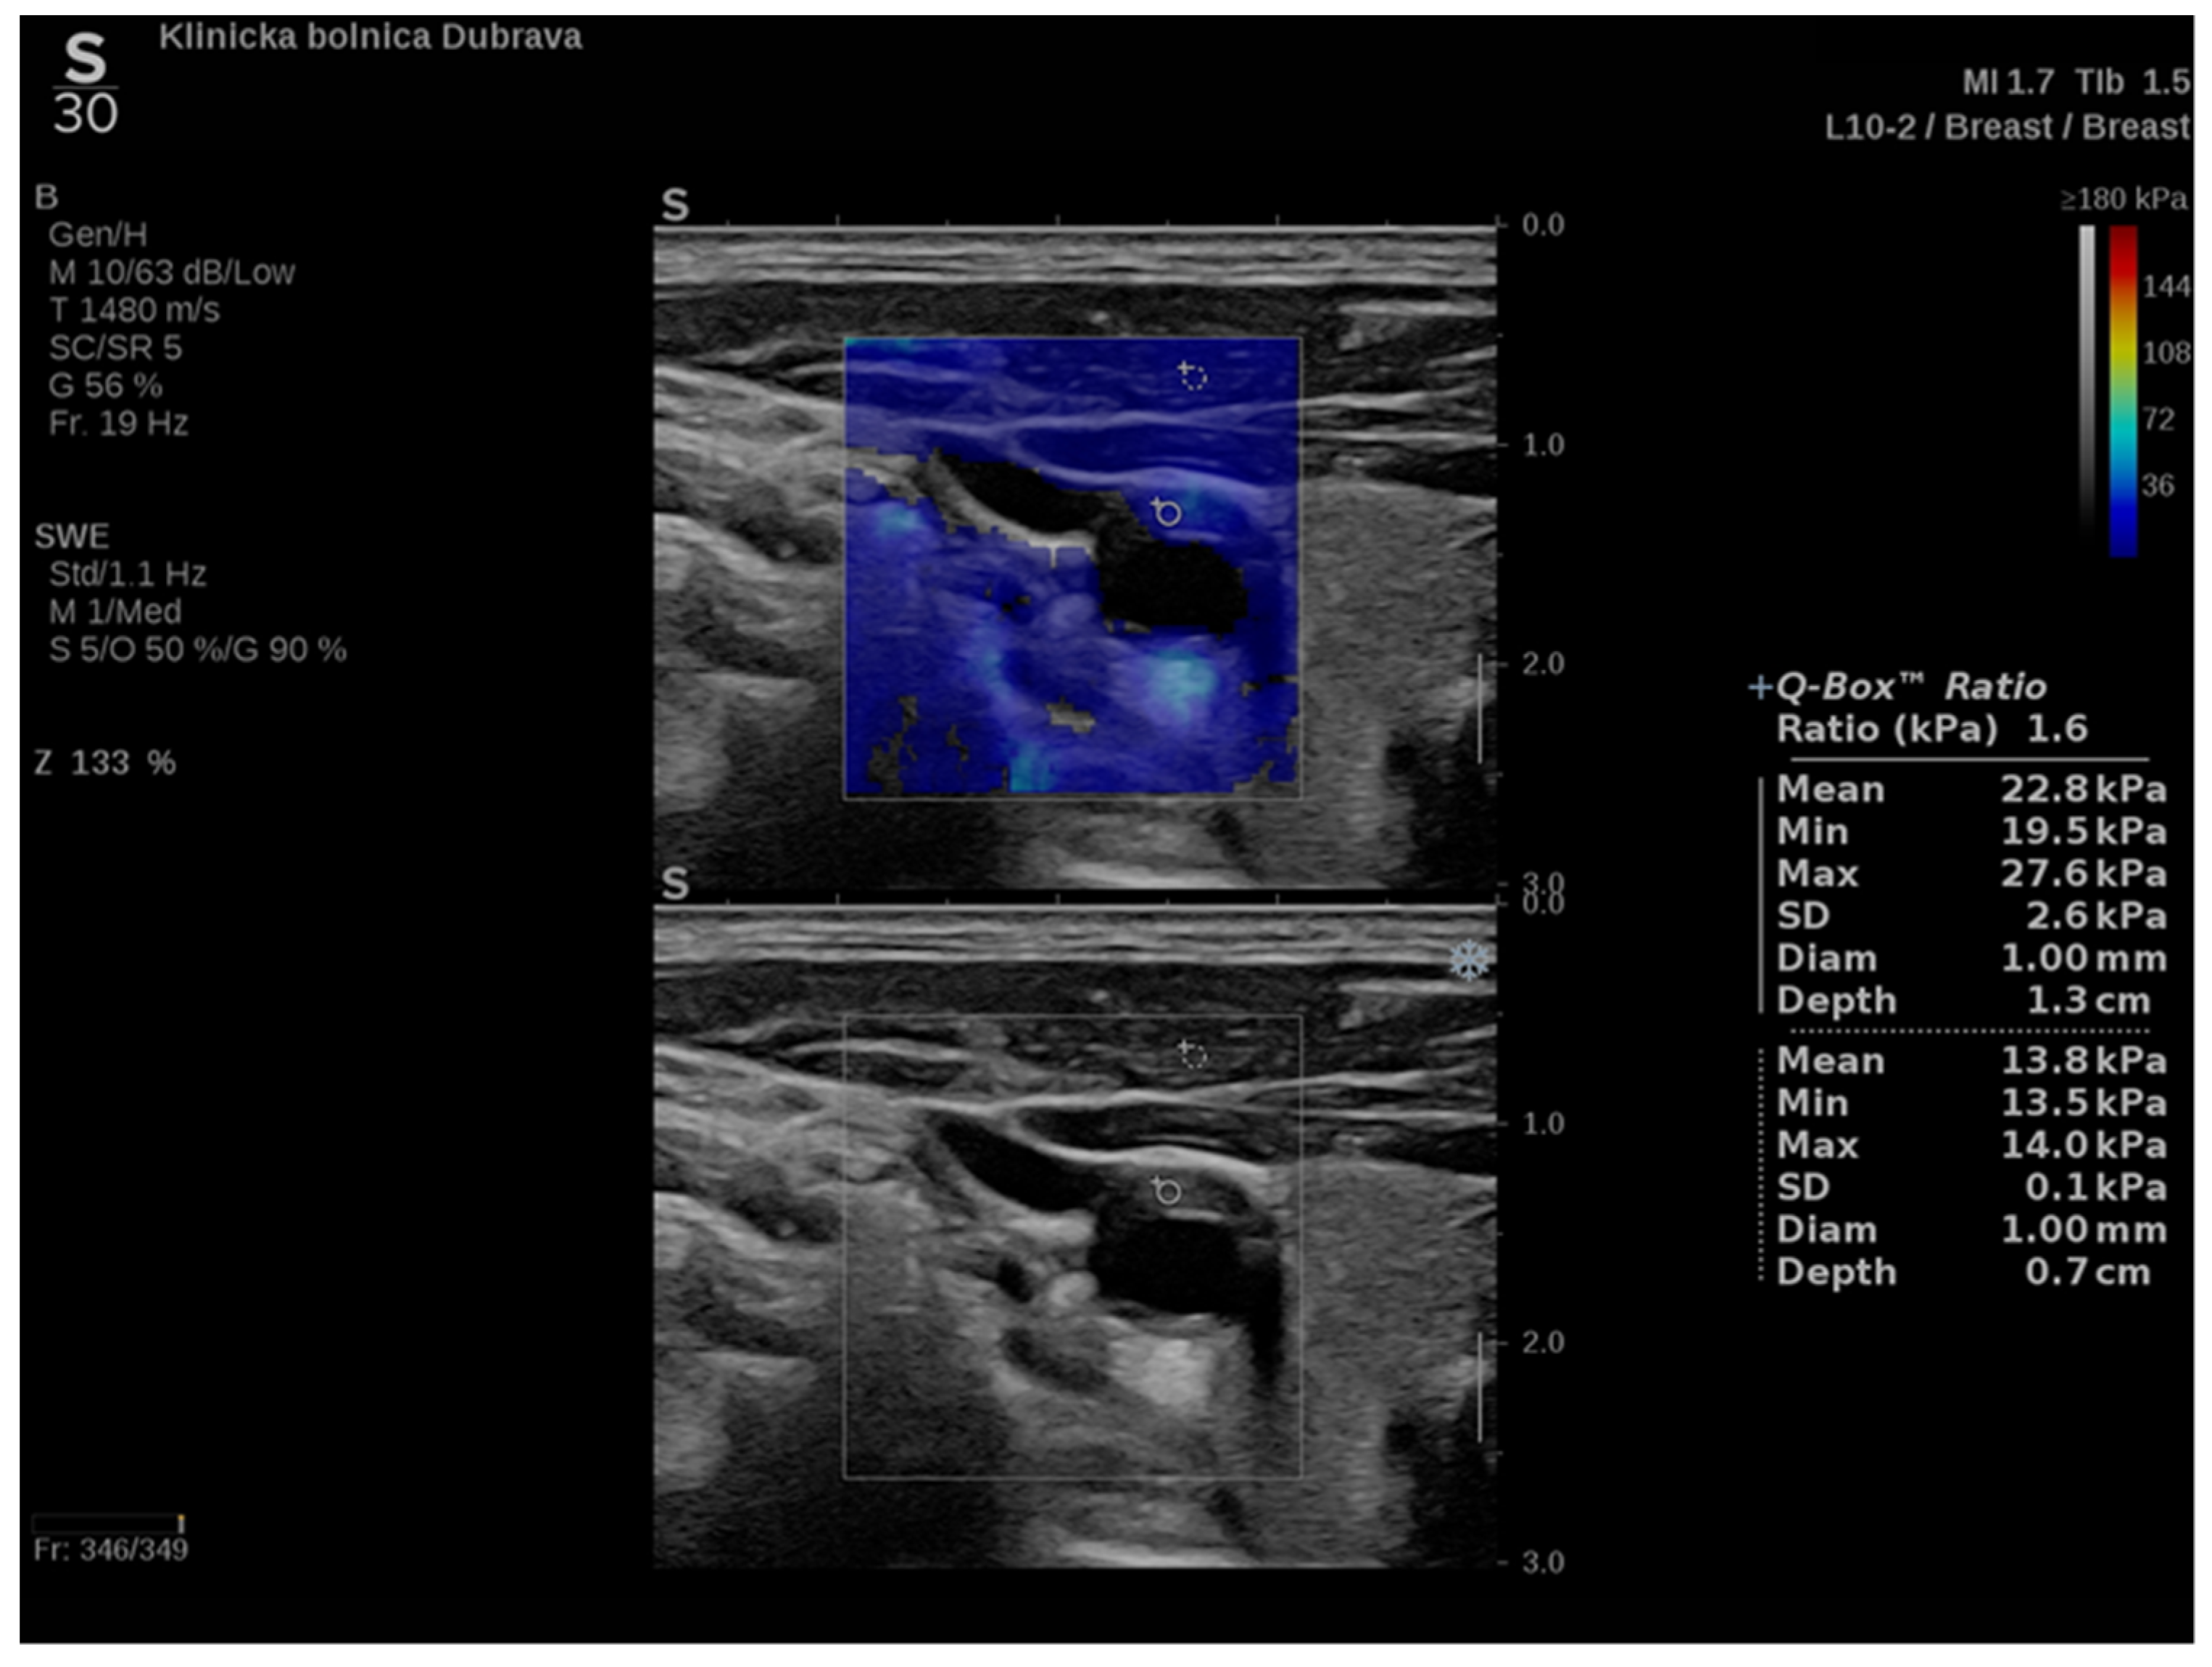

In addition to conventional, Doppler and contrast-enhanced ultrasonography, elastography techniques are another area where ultrasound is being increasingly used, this time to assess the elastic properties of the insonated tissue. There are two types of ultrasound elastography: strain and shear wave elastography (SWE). Strain elastography is performed by manual compression using the transducer, which then produces an image based on the resulting displacement of the tissue caused by the compression. However, it is difficult to measure the exact amount of the applied force during compression, resulting in the method being difficult to standardize. Additionally, the absolute elasticity values cannot be calculated, and only qualitative results can be obtained. Unlike strain elastography, SWE is a type of ultrasound elastography where the elastic properties of the insonated tissues can be expressed both qualitatively and quantitatively (Figure 1 and Figure 2) [22].

Figure 1. An example of an ultrasound examination with shear wave elastography of a segment of the distal right CCA in the longitudinal view with B-mode ultrasound at bottom and shear wave elastography at the top where the elastic properties of the examined tissues (carotid artery wall and surrounding soft tissues) are displayed qualitatively by benign color-coded and superimposed on the B-mode image. Red color denotes the stiffest areas with the highest elastic modulus values.

Figure 2. Another example of an ultrasound examination with shear wave elastography of a segment of the CCA, this time in the transverse view. A carotid artery plaque is visible in the wall of the CCA and displayed with B-mode ultrasound at the bottom and shear wave elastography at the top. In this figure, the elastic properties of the examined tissues are displayed both qualitatively and quantitatively. Quantitative measures are visible on the right-hand side of the picture, measured using two regions of interest, one centered over the plaque and another over the adjoining soft tissues, and an elasticity ratio between the two is calculated by the ultrasound device.